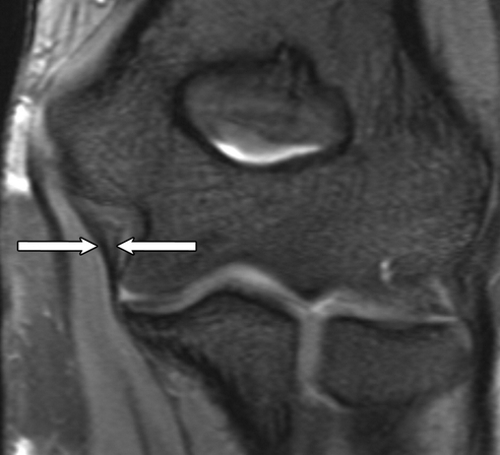

Диагностические мероприятия

Определить степень растяжения может врач-травматолог или хирург. Квалифицированный специалист способен при визуальном осмотре оценить характер и тяжесть травмы. Для первой и второй степени растяжения дополнительная диагностика не требуется. Однако третья степень, сопровождающаяся осложнениями, такими как разрывы связок, вывихи и переломы, требует уточнения диагноза с использованием специализированных методов:

- рентгенография локтевого сгиба и других участков руки;

- компьютерная томография для оценки повреждений суставных связок;

- ультразвуковое исследование мышечных волокон;

- магнитно-резонансная томография;